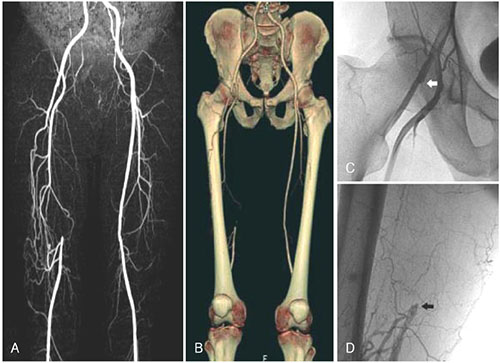

Απεικονιστικές εξετάσεις για τη διερεύνηση της διαλείπουσας χωλότητας αποτελούν το έγχρωμο duplex (triplex), η αξονική αγγειογραφία, η μαγνητική αγγειογραφία και η ψηφιακή αφαιρετική αγγειογραφία.

Σε περιπτώσεις διαλείπουσας χωλότητας μη περιοριστικού τύπου συνήθως η θεραπεία είναι συντηρητική. Αυτή περιλαμβάνει φαρμακευτική αγωγή, ρύθμιση παραγόντων κινδύνου, διακοπή του καπνίσματος και επιτηρούμενο πρόγραμμα άσκησης. Σε περιπτώσεις κρίσιμης ισχαιμίας ή σοβαρής διαλείπουσας χωλότητας η αντιμετώπιση είναι συνήθως επεμβατική, είτε με αγγειοπλαστική με ή χωρίς stent, ή χειρουργική.